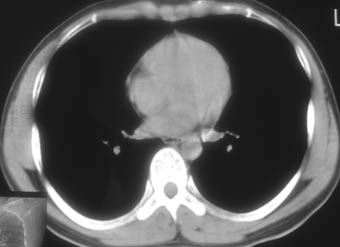

纵隔窗!

右肺下叶背段斑片状阴影,边缘模糊,纵隔内未见肿大淋巴结,病人无发热及感冒史,要考虑浸润型肺结核,可结合ppd检查,或短期抗炎治疗复查。

右肺下叶背段长椭圆型病灶,边缘较规则,无明显分叶征、毛刺,远段未见阻塞征象,病灶较松散,纵隔窗明显小于肺窗,年龄35岁,支气管稍示变窄,纵隔内未见明显肿大淋巴结,这些都不支持肿瘤。病人无任何感觉,无明显发热感冒病史,首先考虑结核(也是结核好发部位),慢性炎症不能完全除外。